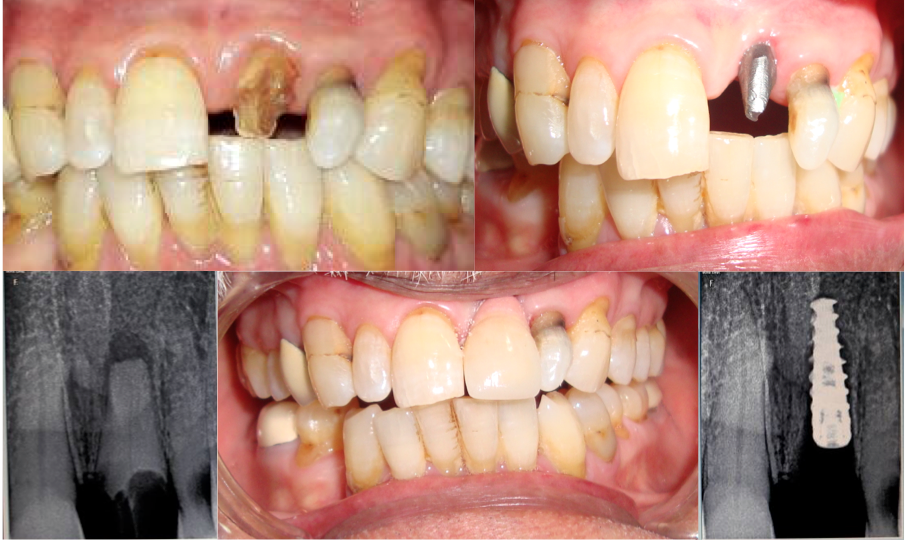

Single Tooth Replacement

Card image